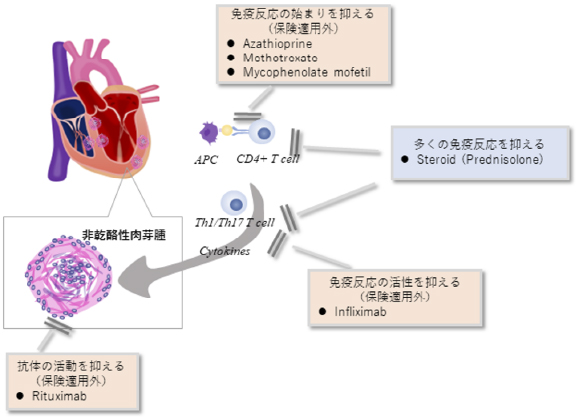

サルコイドーシス

サルコイドーシスは、非乾酪性肉芽腫という病理変化を伴う炎症性疾患です。心臓以外にも眼、皮膚、肺やリンパ節に起こり得ます。心臓においては、心筋の収縮障害から進行すれば心拡大が起きます。不整脈を併発しやすいことも知られています。診断には心臓MRIや血液検査のほかに、心臓にブドウ糖が取り込まれているか調べる核医学検査であるFluorodeoxyglucose-Positron Emission Tomography(FDG-PET)が病勢の把握に有用です。

サルコイドーシスの治療は免疫や炎症を抑えるステロイドが一般的です。そのほかの免疫抑制剤が効果を発揮することもありますが、本邦では保険適用外です。

ステロイド治療により炎症・免疫反応が軽減